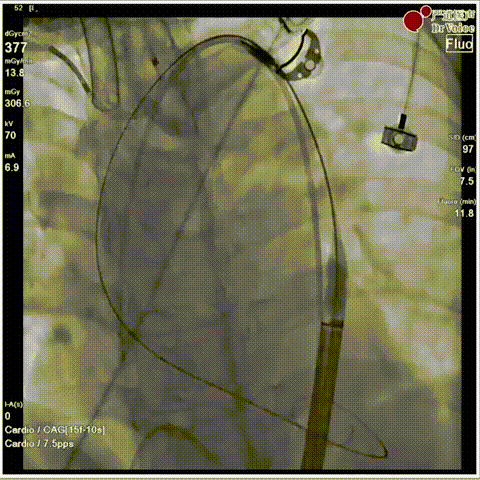

手术瓣膜释放后造影(4例)

病例一

病例二

病例三

病例四

快速过弓跨瓣(4例)